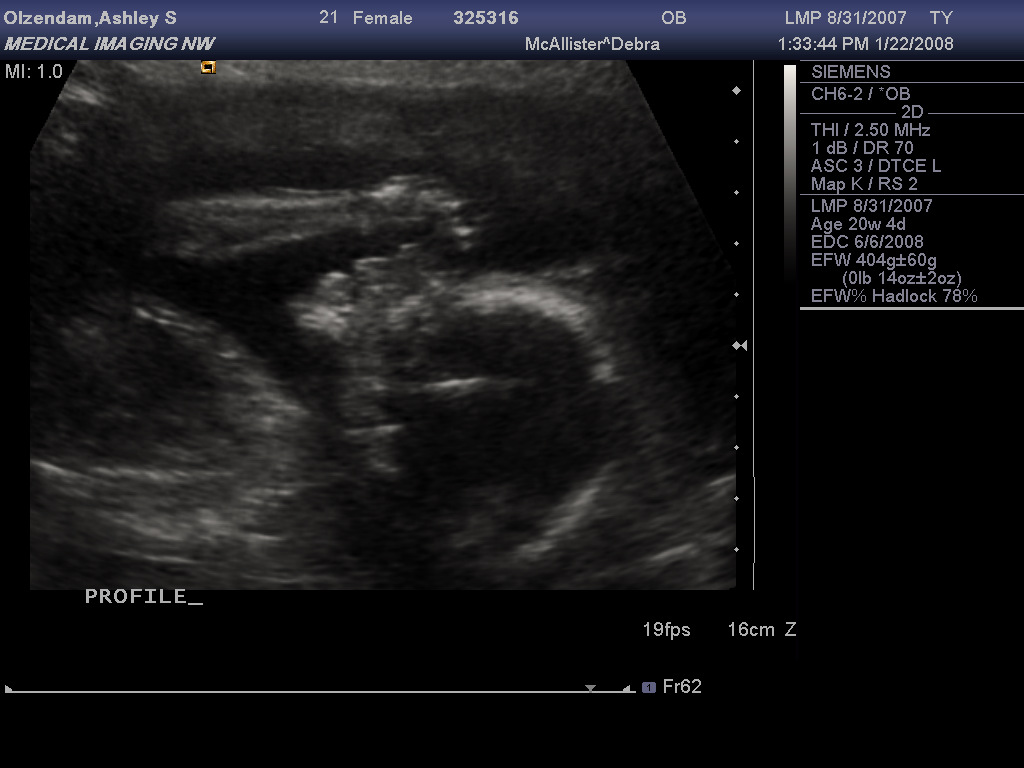

Had an ultrasound this afternoon and all the parts are where they should be. However, the baby was a bit uncooperative, and refused to part its legs for the technician to take a peek, so we're still unsure of the sex. I think Stiofain has been conspiring with the baby while I sleep (he didn't want to know). :lol:

Profile with  Arm.jpg

In the top pic, the baby is so giving you the bird. :P